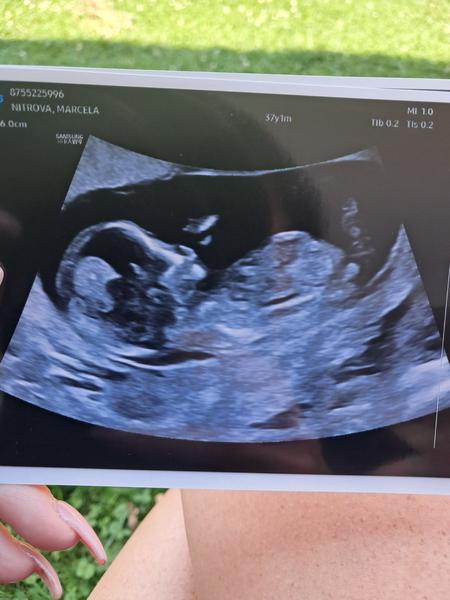

Holky jsem 14tt a podle ultrazvuku tipujete holka či kluk? 🙂